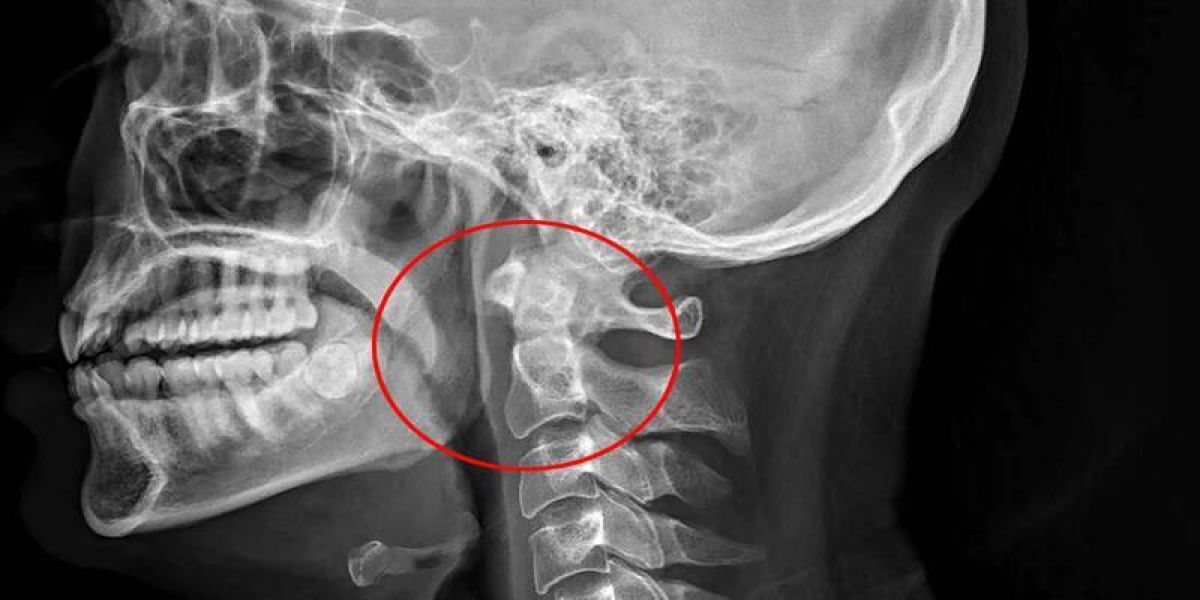

Segundo o IFLS, o caso foi descrito em um relatório médico com o título de "Estalos: quando espirrar leva à crepitação no pescoço”.Ele também passou a sentir dor de garganta, dificuldade para engolir e até mesmo uma mudança na voz. Após um exame, foi descoberto que, durante o ato de suprimir o espirro, ele rompeu a nuca, criando bolhas de ar dentro de seus tecidos profundos e músculos.A ruptura – que geralmente é causada por traumatismo cervical contuso, vômitos profusos e tosse forte – fez com que o ar vazasse para a região retrofaríngea (veja a seta na imagem acima).